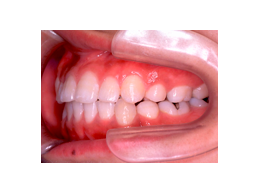

叢生 治療後

歯を抜いたスペースを利用して、残りの歯をきれいに並べ替えてゆきます。この患者さんの場合は、抜いたスペースはほとんど余りませんので、意外に早く治療が終わりました。